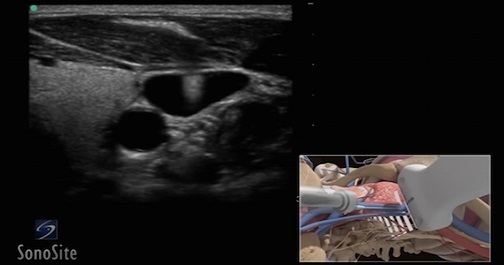

Central Line Management Program

Central Line placement is one of the most common hospital procedures, and yet it is not without risk. Ultrasound-guided Central Venous Catheter (CVC) placement reduces some of the more severe risks, such as pneumothoraces and CLABSI. Learn the procedures, techniques, and best practices associated with placing a central line under ultrasound guidance while minimizing risks of iatrogenic complications.